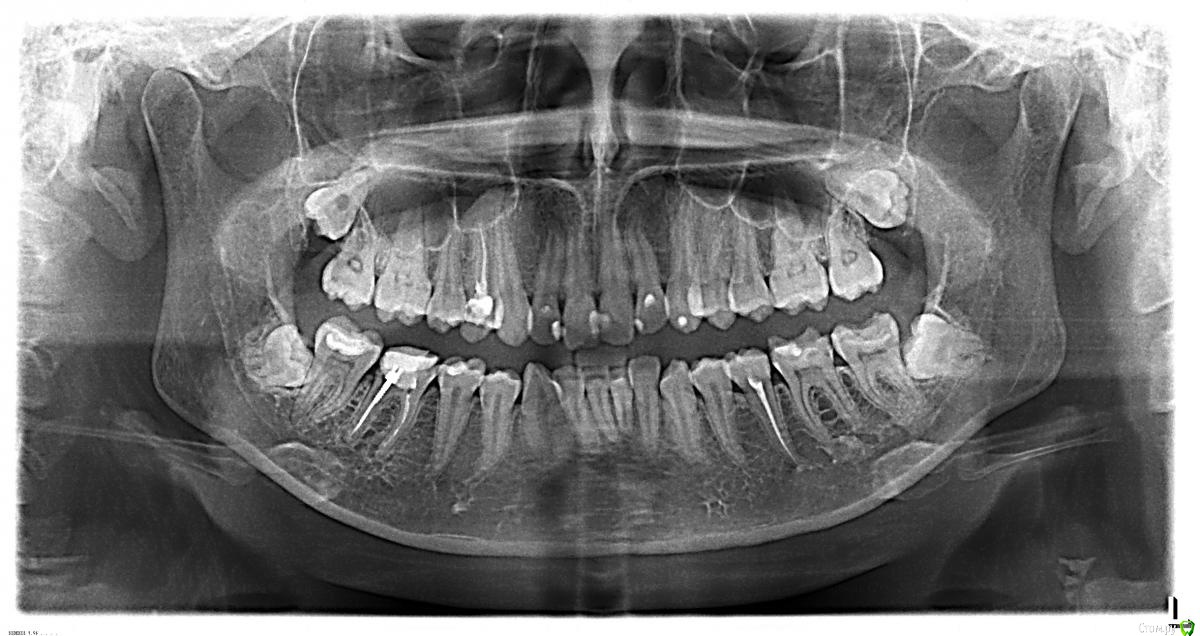

oksanavlasenko87 Опубликовано 21 августа, 2015 Поделиться Опубликовано 21 августа, 2015 (изменено) Добрый деньСитуация такая :4 месяца назад удаляли 8-ки ,лежащие горизонтально под десной.После удаления онемела губа ,нижняя челюсть слева и подбородок,т.е не прошло после анестезии.Проколола уколы мильгамма, стало лучше .но не до конца.5 дней назад лечила зубы на той же стороне,коренные, и на этот раз онемела половина языка! Сегодня снова лечили зуб на левой стороне, доктор сделал анестезию , зная ситуацию , сделал укол в десну рядом с зубом, сказал , что отключит только один зуб, и вот через 20 секунд у меня второй раз онемела половина губы и подбородок ! Прошло 5 часов, никаких признаков жизни ..А я только недавно проколола курс мильгаммыПожалуйста скажите , что может быть причиной? До удаления восьмерок все было в порядке, выкладываю снимки ДО и ПОСЛЕ Изменено 21 августа, 2015 пользователем oksanavlasenko87 Ссылка на комментарий